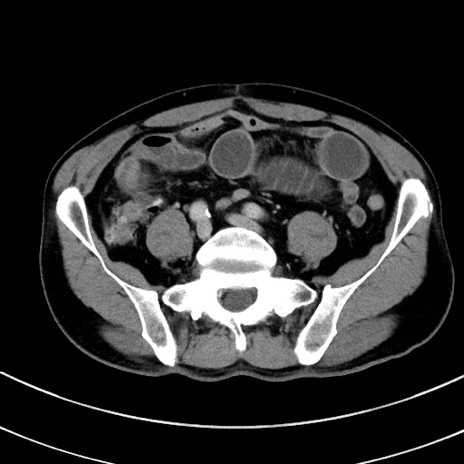

症例8(横断像)

【症例】 60歳代男性

【主訴】 黒色吐物

【現病歴】 4日前から嘔気自覚、2日前の朝食後にも嘔気あり、自分で手で嘔吐反射起こし嘔吐したところ血が混ざっていたため受診。

【既往歴】 5年前汎発性腹膜炎を伴う急性虫垂炎で手術、高血圧、前立腺肥大症、高脂血症

【身体所見】 腹部正中に手術癩痕あり 腹部平坦・軟圧痛なし膨満感あり

【データ】WBC 8400、CRP 4.54